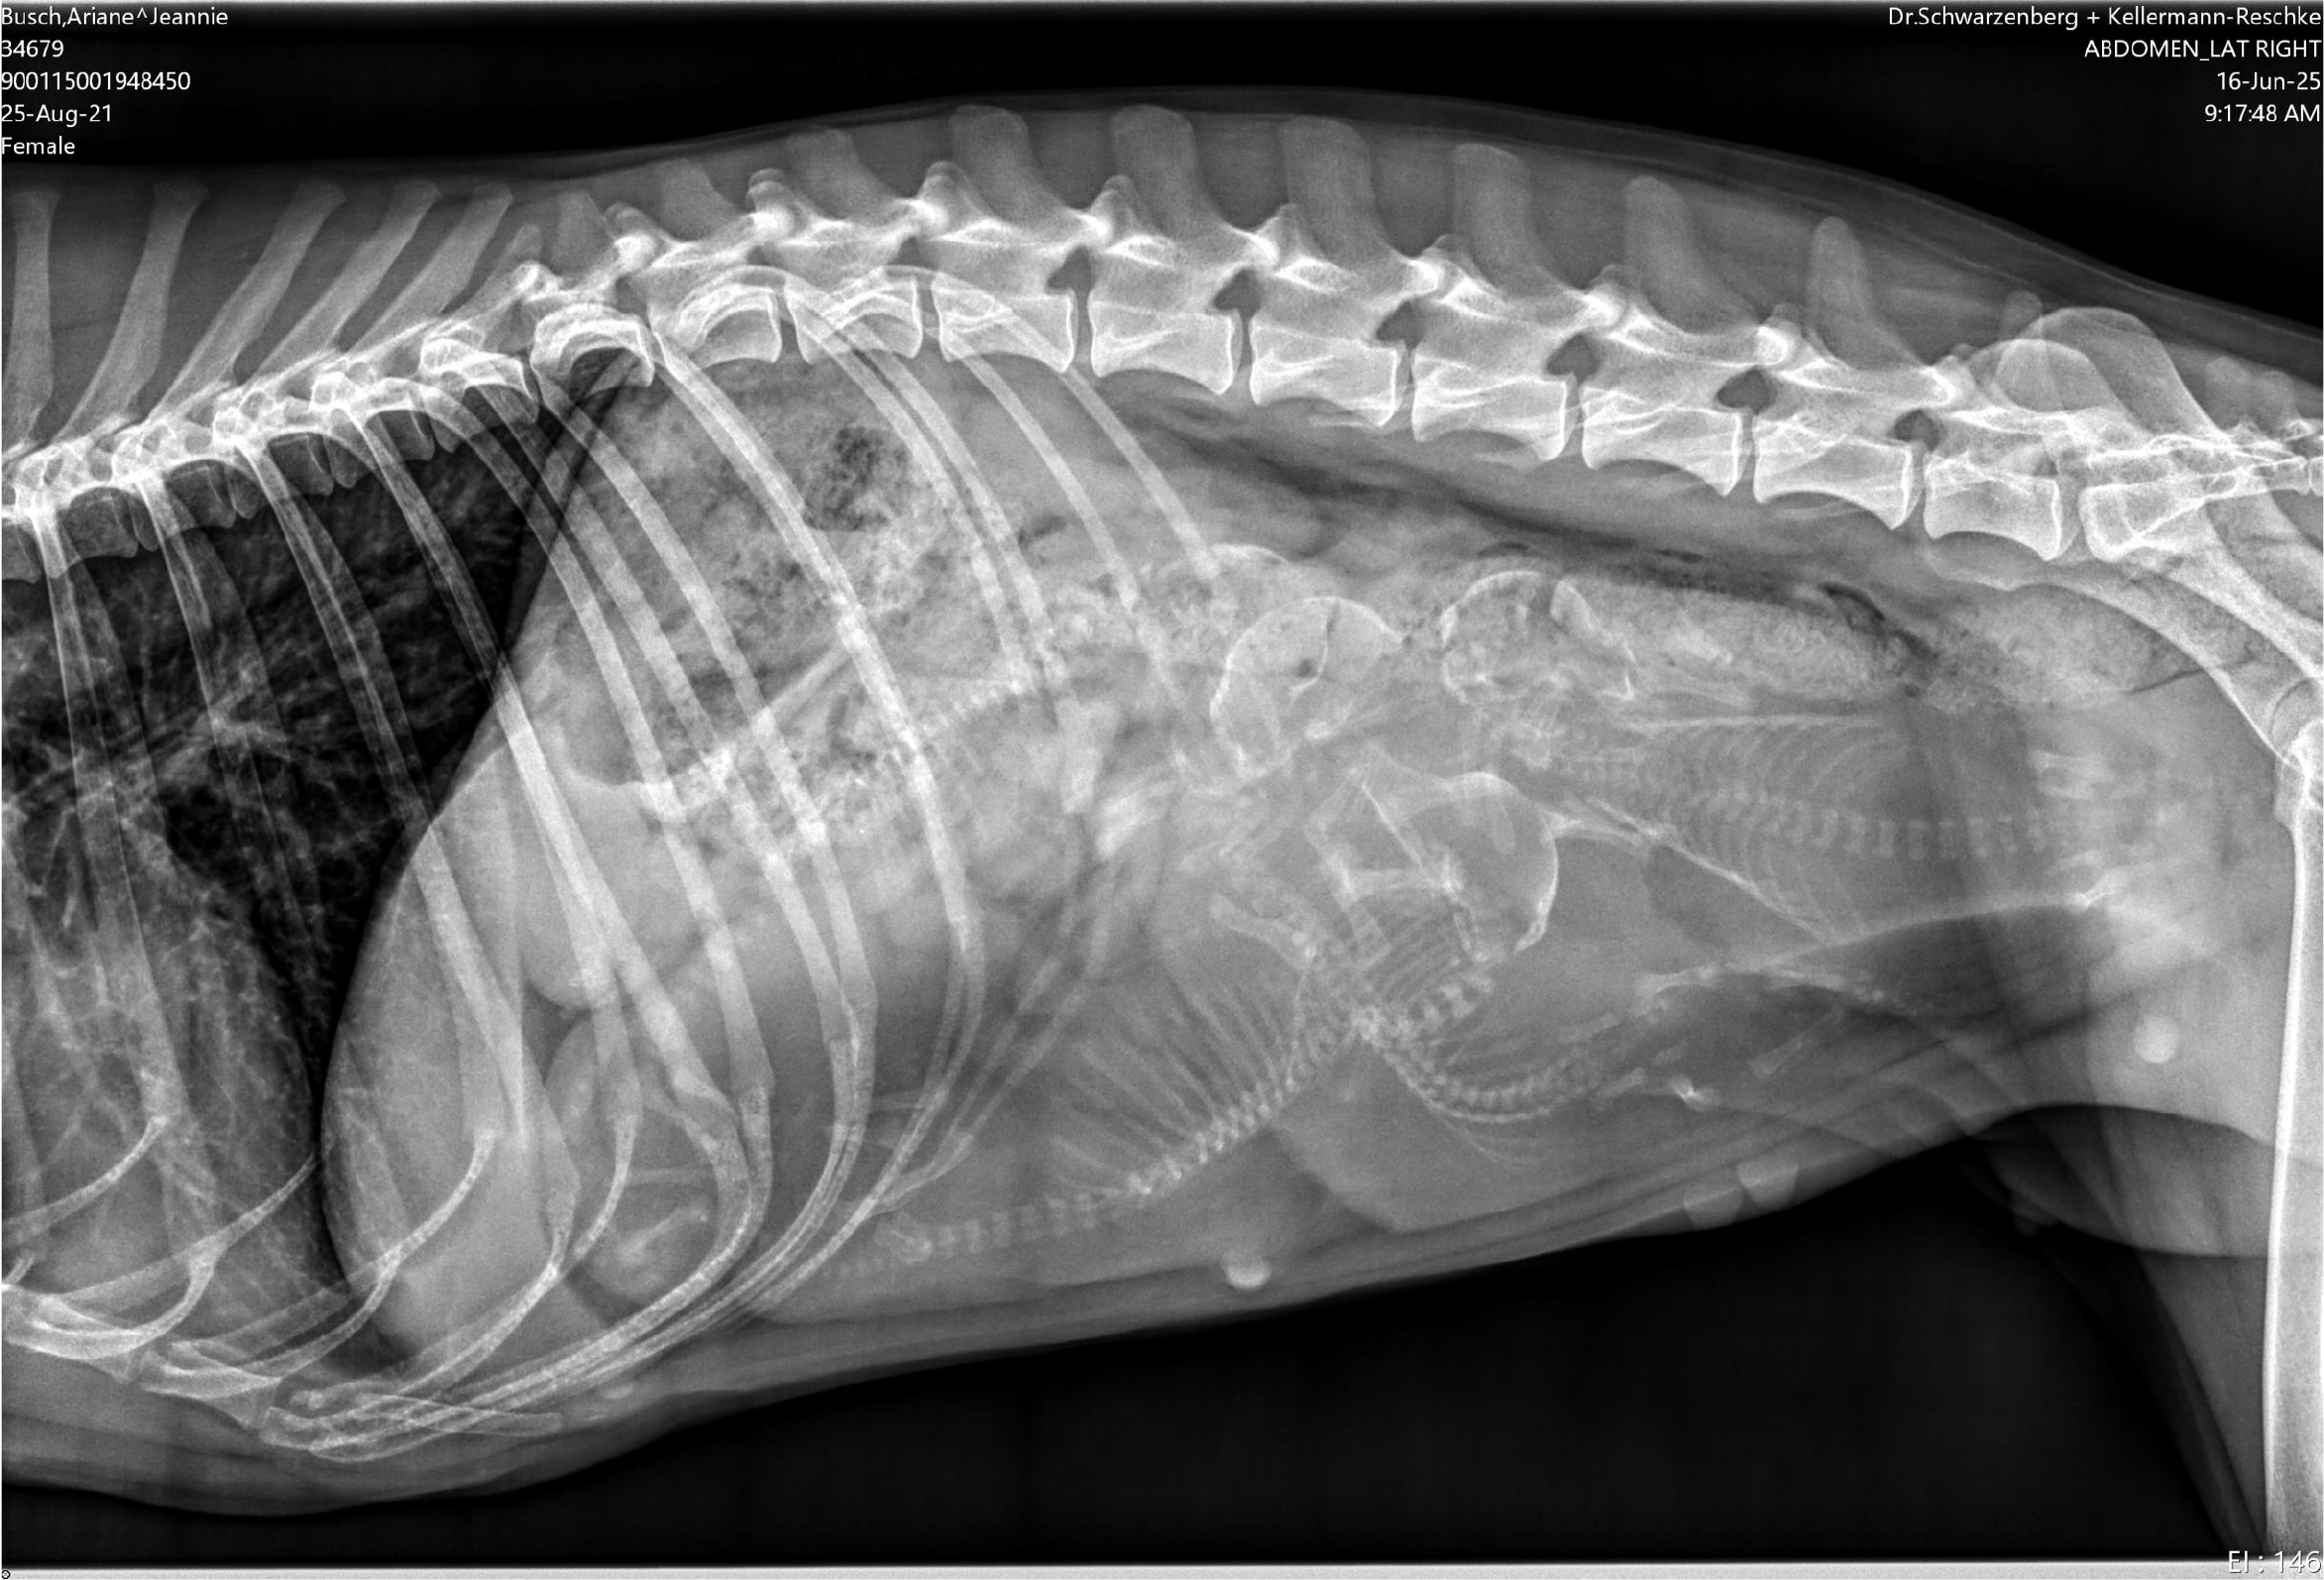

Unsere bezaubernde Jeannie „Tova‘s Riesling Surprise in Germany“ wurde Ende April von unserem charmanten Mio „Golden Nugget's Achilles“ gedeckt.